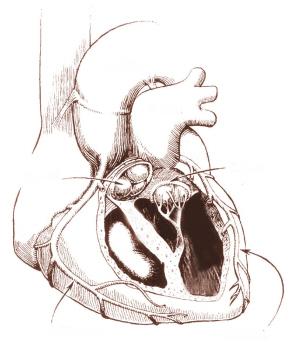

经仔细检查,除了二尖瓣关闭不严,童童并没有其他心脏畸形问题,陈振强主任决定为患儿手术。但手术前,必须先要使患者的心衰问题得到改善。医生为童童输注白蛋白,强心利尿,扩血管,以改善心功能,在做好充分准备下,8月15日上午,陈振强带领手术组医务人员为童童进行二尖瓣瓣膜置换术。

陈振强昨日回忆说:“这是一个非常罕见的病例,我反复研究孩子的超声心电图,仔细检查了三次,没有看过这么严重的瓣膜病,到底是什么原因引起的,心里也在猜测。在手术台上,我拿着手术刀,还在和麻醉师说,希望不会出现其他意外。但是心脏打开来一看,里边心内膜是发白的,这是硬化的表现,我一下意识到这是“心内膜弹力增生症”,这是非常罕见的病变,以前我在一位成年心脏病患者身上曾经看到过。心脏瓣膜是一个“门卫”,很有弹性,像糯米纸样薄,在血液流过后,瓣膜就会合上。但是这位小患者的瓣膜严重硬化,整个心脏瓣膜增生,像牛皮纸一样,没有一点弹性。心脏这个“门卫”把关不严,导致血液返流,心脏急剧扩大。我们为其置换了人工瓣膜,使人工瓣膜在心脏收缩的时候能够自然关闭。因为孩子太小,缝合瓣膜过程中必须十分仔细。”陈振强介绍说,手术以后,人工瓣膜不会再出现增生情况,但童童长到十几岁时还要再换一次瓣膜,以适应心脏生长的需要。